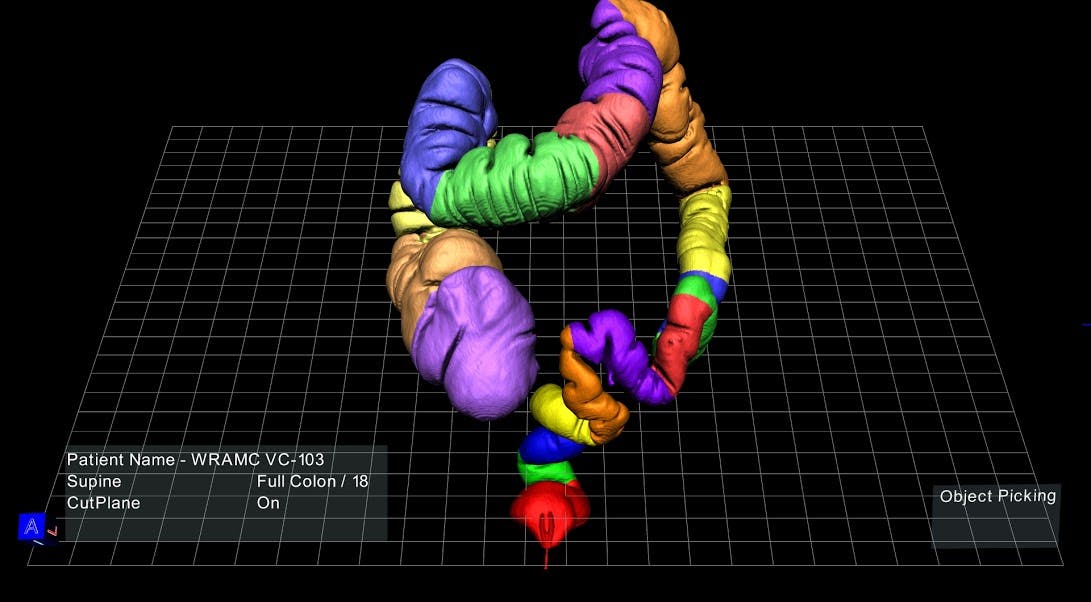

If you or I could look at a 3D model of a patient’s colon, divided into neatly color-coded segments and floating on a screen in front, we probably wouldn’t marvel at the anatomical intricacies of the large intestine. We’d more likely be drawn to the novelty of this immersive, unfamiliar technology—even if it requires wearing plastic glasses similar to those from 3D movies in the ’90s, sans red and blue cellophane.

The software can transform data from ultrasound, CT, and MRI scans into three-dimensional anatomical models projected onto a computer screen, with which doctors can interact using a stylus. A doctor can, for example, click on one brightly colored segment of the virtual colon to scan the interior tissue for soft, spongy polyps, or point and click to extract an aneurysm from deep inside a virtual brain.

Take that colorful model of the colon: It was created for an experimental virtual colonoscopy protocol in which Judy Yee, MD, an associate professor of radiology at UCSF, used the 3D model—quickly synthesized from hundreds of CT images—to scan a patient’s intestinal tract for lesions. Dr. Yee was able to reduce the procedure time from an average of 30 to 40 minutes to around five to eight, while two junior radiologists in her lab were able to complete the procedure in 10 or 15, Aguirre explained.

That said, Dr. Napel agreed that the technology holds great promise in areas like virtual colonoscopy, citing Dr. Yee’s work with the platform. “EchoPixel has created a way to actually float sections of the large intestine in front of the screen and allow radiologists to spin them around and look at those surfaces really efficiently. That’s an example where it could be very, very effective.”